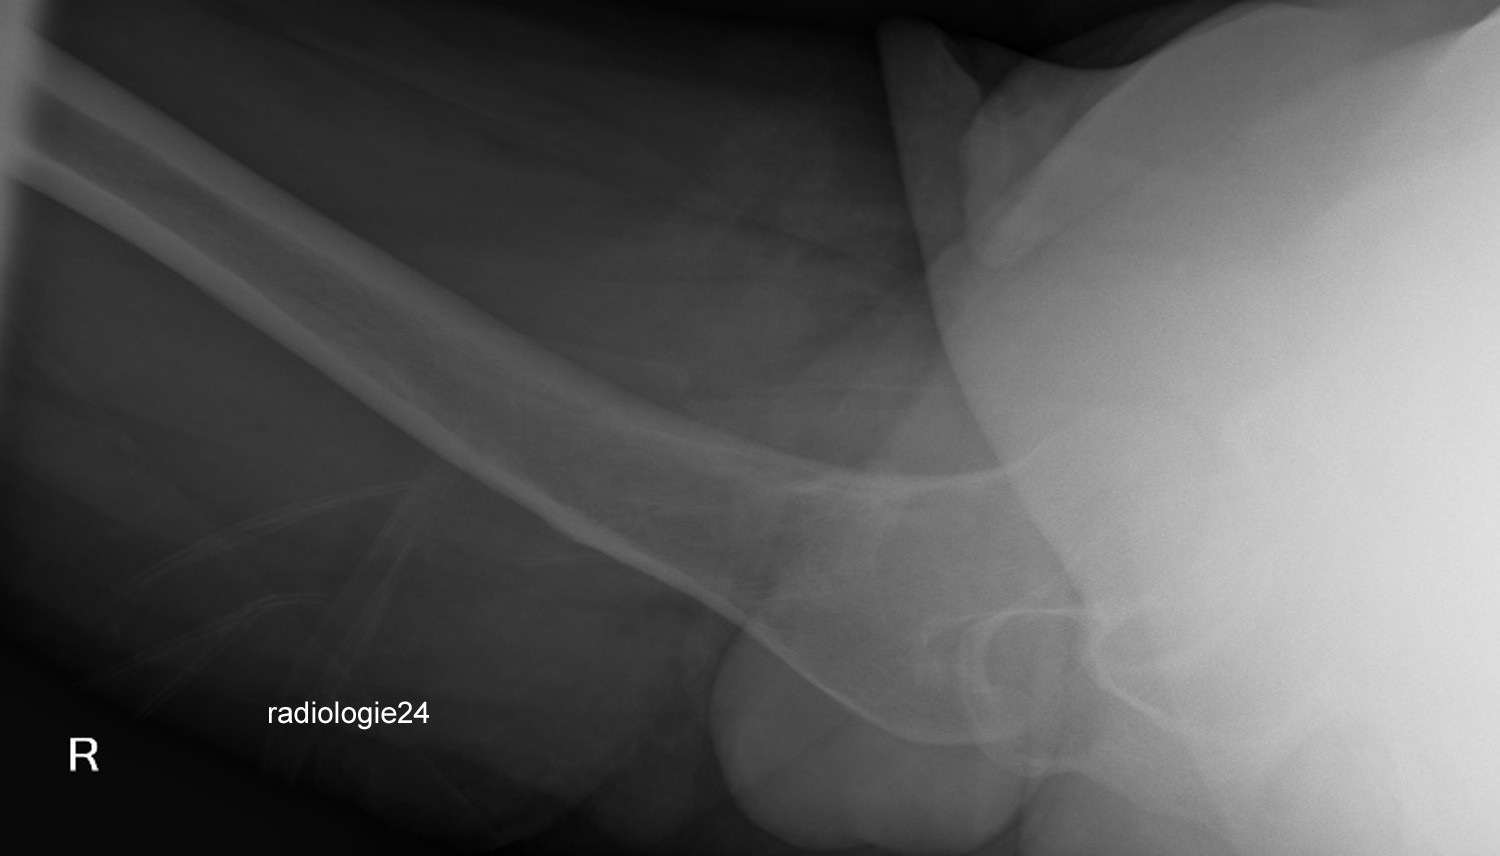

Röntgenfall des Monats Oktober 2018 mit Auflösung

34 jährige Patientin.

Progrediente Schmerzen in beiden Hüftgelenken. Z.n. Sturz.

Ihre Diagnose?

Weitere radiologische Diagnostik notwendig?